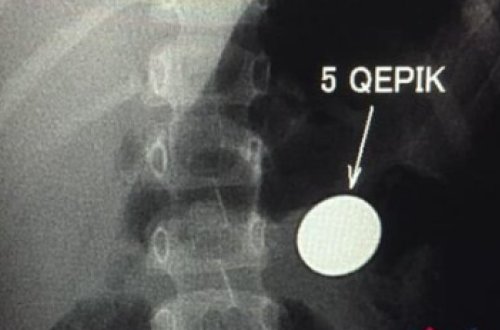

Bakıda 4 yaşlı uşağın mədəsində qəpik AŞKARLANDI

2244

qəpik

7news

yolla

mədədən

uşağın

mədəsindən

uşaq

görə

çıxacaq

xəbər

olduğuna

qəpiyin

mədənin

diametri

çıxmır

mədədir

etdik

aşkar

müayinəyə

hələ